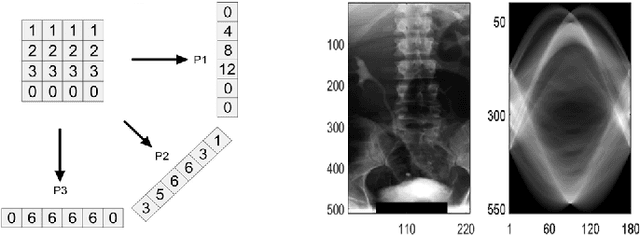

Abstract:Radon transform and its inverse operation are important techniques in medical imaging tasks. Recently, there has been renewed interest in Radon transform for applications such as content-based medical image retrieval. However, all studies so far have used Radon transform as a global or quasi-global image descriptor by extracting projections of the whole image or large sub-images. This paper attempts to show that the dense sampling to generate the histogram of local Radon projections has a much higher discrimination capability than the global one. In this paper, we introduce Local Radon Descriptor (LRD) and apply it to the IRMA dataset, which contains 14,410 x-ray images as well as to the INRIA Holidays dataset with 1,990 images. Our results show significant improvement in retrieval performance by using LRD versus its global version. We also demonstrate that LRD can deliver results comparable to well-established descriptors like LBP and HOG.